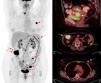

En el cáncer epitelial de ovario avanzado surge la necesidad de seleccionar a las pacientes con estadios más avanzados (IIIc y IV), que presentan enfermedad más allá de la cavidad abdominal. La detección mediante técnicas de imagen de lesiones extraabdominales condiciona un importante cambio de estrategia terapéutica, puesto que estas pacientes dejan de ser candidatas a una cirugía primaria como primera opción terapéutica y son candidatas a quimioterapia neoadyuvante. En la práctica habitual, la estadificación prequirúrgica se realiza mediante TC, presenta una elevada eficacia en la detección de carcinomatosis peritoneal, especialmente en las lesiones inferiores a 5mm o con diseminación miliar y en los implantes y nódulos mesentéricos18. En comparación con la TC, el estudio mediante PET-TC permite identificar con una sensibilidad similar las lesiones intraabdominales pero mejora la detección de lesiones extraabdominales (fig. 1), que suponen un cambio en el estadio de la enfermedad, y la convierten en un estadio iv19. Queda por determinar si este aumento en el estadio y la posible modificación del abordaje terapéutico en estos casos tiene impacto en la supervivencia global de las pacientes.

Estadificación pretratamiento de cáncer de ovario. Paciente de 48 años con diagnóstico por TC de carcinomatosis peritoneal de origen ovárico o carcinoma primario peritoneal. Se realiza PET-TC de estadificación previamente al tratamiento. La imagen de cuerpo entero de PET (izquierda) muestra captación aumentada de FDG en una masa ovárica izquierda (flecha) e implantes peritoneales (asterisco) pelvianos (derecha, arriba) y en colon ascendente (centro). En la región torácica, se visualizan implantes pleurales derechos (centro; flecha discontinua) y en adenopatías cardiofrénicas y mediastínicas (derecha, abajo; punta de flecha), que contraindican la cirugía citorreductora como tratamiento primario.